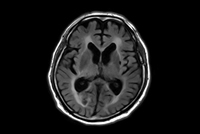

NeuroQuant

-